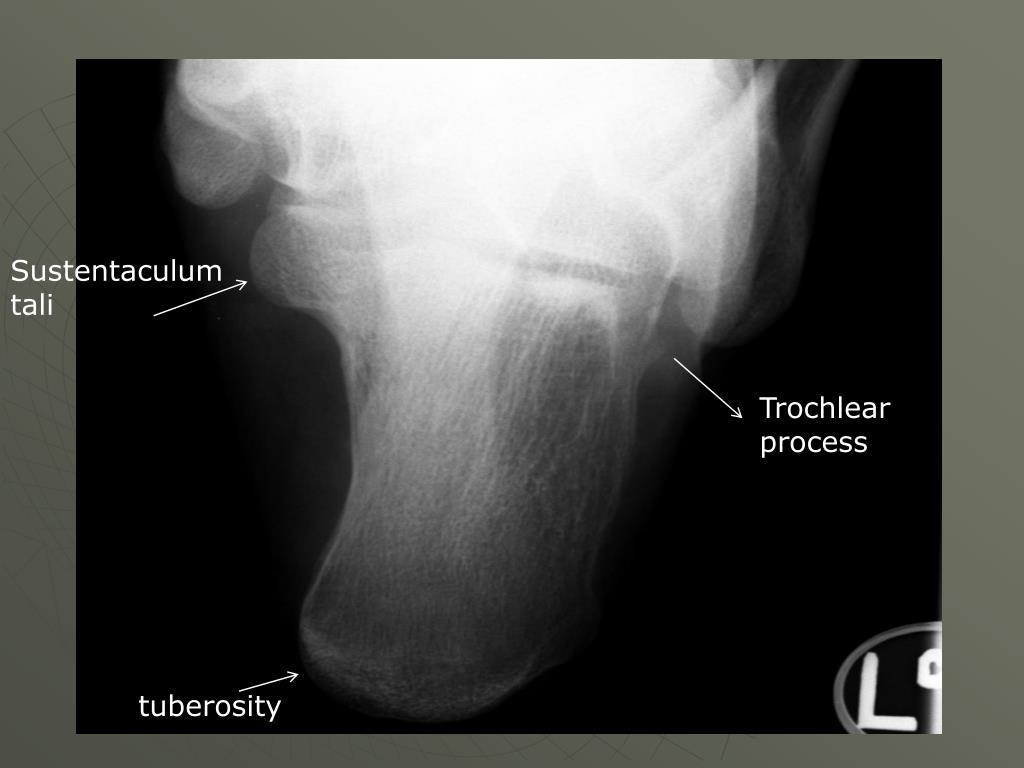

34. Sustentaculum tali Trochlear process tuberosity

35. Structures shown: • An axial projection of the calcaneus ***from the tuberosity to the sustentaculum tali and trochlear process

36. AP Axial Right Calcaneus

37. Check for: • Calcaneus should be visualized to include the talocalcaneal joint • No rotation of calcaneus (check the first or fifth metatarsals) • Density to see joint without burn out of tuberosity (two films if not using DR or CR)